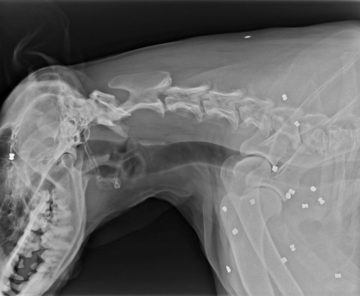

Doslova s opovrhnutiahodným správaním k zvieraťu sa stretli pracovníci piešťanského zvieracieho útulku. V utorok minulý týždeň im obyvatelia obce Banka…